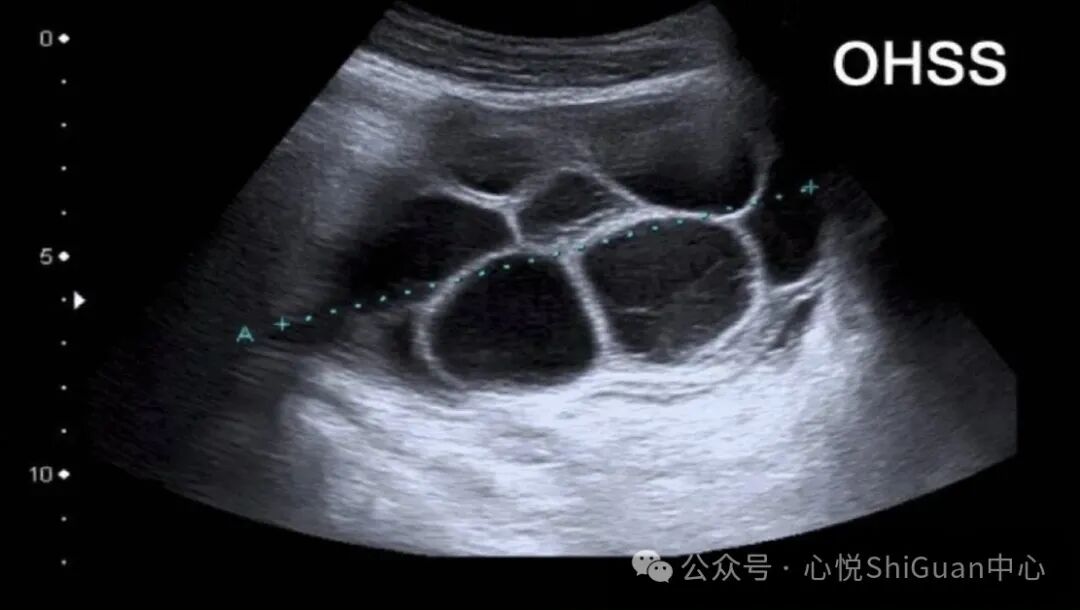

2. 卵巢过度刺激综合征(OHSS)

部分女性在使用促排卵药物后,可能会出现卵巢过度刺激综合征。此时卵巢体积增大,血管通透性增加,容易导致出血,并可能伴有腹痛、腹水、水肿等症状。